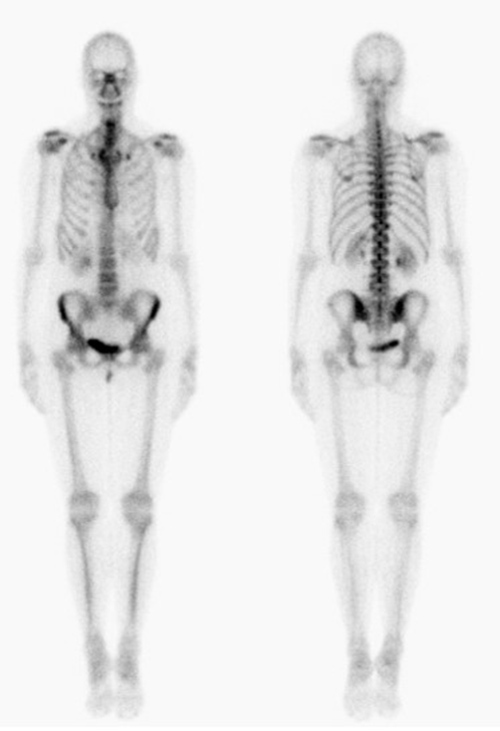

While FDG is an analog of glucose, the fluoride in NaF incorporates into the hydroxyapatite (mineral component) of bone by replacing a hydroxyl group to form fluoroapatite. F18-NaF PET bone scan commonly demonstrate non-malignant, scattered focal uptake within the spine, bilateral knees, feet and shoulder joints, consistent with degenerative bone remodeling. Normally, there is no brain uptake on NaF PET scanning.

A) Whole-body F18-FDG PET scan maximum intensity projection (MIP) bone demonstrates intense uptake in the brain and renal excretion. Mild activity is seen within the bone marrow. B) Whole-body F18-NaF PET bone scan maximum intensity projection (MIP) demonstrates scattered focal uptake within the spine, bilateral knees, feet and shoulder joints consistent with degenerative bone remodeling. Note: Intense uptake is seen within the brain on FDG PET and no uptake is seen on NaF PET. |